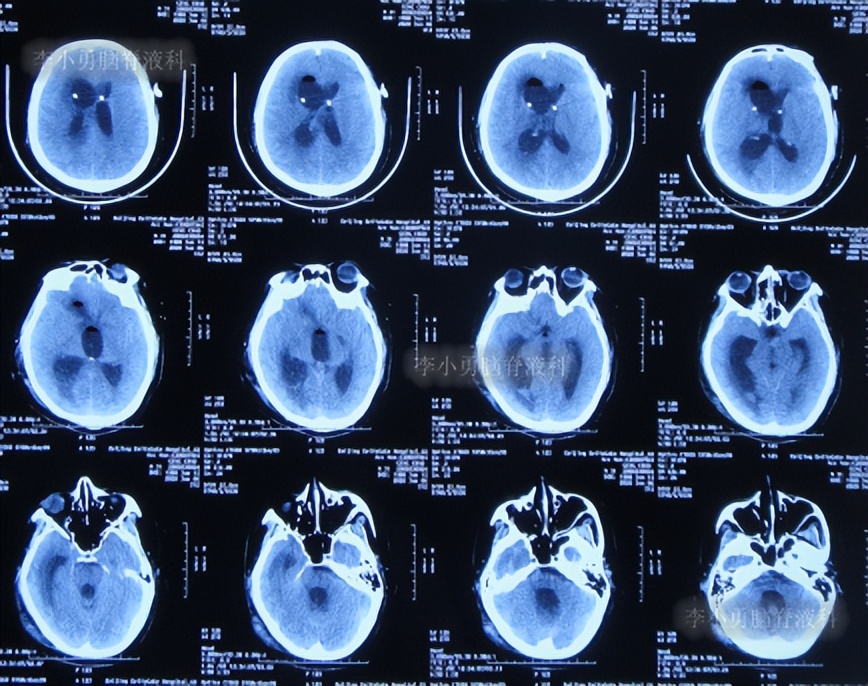

出院后1年半期间,仍时有视物重影的症状,并未给予处理,但到2019年9月27日(脑室腹腔分流术后1年零6个半月),出现头晕,恶心呕吐,视物重影加重,5天后因症状无缓解,就诊于当地的河南省临颍县某医院,查脑CT示脑积水(图-1);给予腰穿检查示颅内压力高220mmH2O。

图-1:2019年10月3日头颅CT